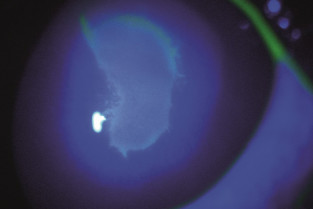

- Reconnaitre et traiter un ulcère à bords décollés.

Ces ulcères cornéens qui ne guérissent pas